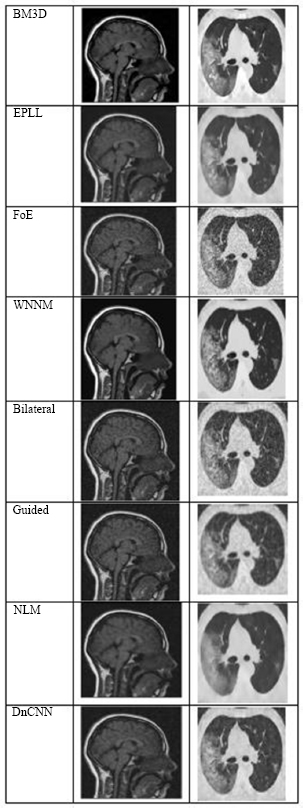

Fig. (4) shows the results at a noise variance of 0.01, where it has been observed that all algorithms produce clear images, except for the Guided algorithm.

Fig. (5) shows the results at a noise variance of 0.05, where it has been observed that the BM3D, EPLL, and WNNM algorithms produce clearer images compared to other algorithms. NLM and DnCNN also perform well, but not as well as the above-mentioned three algorithms.

Fig. (4).

The output of different algorithms at a noise variance of 0.01.

Fig. (5).

The output of different algorithms at a noise variance of 0.05.

Fig. (6) shows the results at a noise variance of 0.09, where it is observed that the BM3D, EPLL, and WNNM algorithms produce clearer images compared to other algorithms. Another algorithm, DnCNN, also performs well, but not so well as the above-mentioned three algorithms.

Fig. (6).

The output of different algorithms at noise variance 0.09.

Fig. (7) shows the results at a noise variance of 0.5, where it has been observed that all the algorithms produce blurred images, except for the BM3D algorithm. However, the results of the BM3D algorithm are not so satisfactory. As a result, it has been observed that at a noise variance of 0.5, none of the algorithms performed well.

Fig. (7).

The output of different algorithms at Noise Variance 0.50.

It has been observed that, except for the Guided Filter, which was unable to preserve edge details successfully, most algorithms presented visually clear and good results at low noise levels (variance = 0.01). Techniques such as BM3D, EPLL, and WNNM consistently produced better quality and detail preservation than others in terms of their visual quality and detail preservation at medium noise levels (variance = 0.05 and 0.09). Although their performances were commendable, those of NLM and DnCNN were slightly less accurate and reliable.

All the algorithms performed poorly at the high-noise level (variance = 0.5), producing significantly distorted and degraded images. At this level of noise, even BM3D, which had demonstrated relative robustness, could not produce outputs appropriate for diagnosis. This result highlights the limitations of current denoising methods in high-noise or low-SNR conditions that are common in low-dose or accelerated medical imaging scenarios.